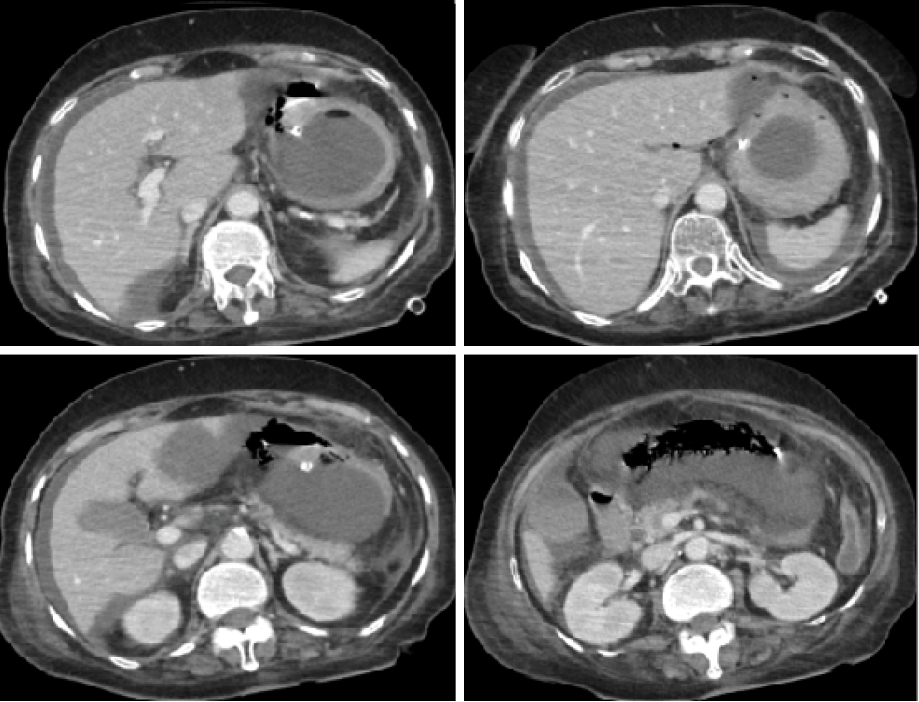

In the COVID-19 ICU, the patient received ceftriaxone, azithromycin, and dexamethasone 10 mg BID. Anticoagulation with low-molecular weight heparin (5000iu BID) was administered. She showed steady recovery throughout her ICU admission. On day nine, coffee-ground material was aspirated through her nasogastric tube despite being on a proton pump inhibitor, so the dose was increased. Her hemoglobin dropped to 8.4 g/dL. On day 11, she was extubated and shifted to the general ward. On the following day, she was again found to have coffee-ground nasogastric aspirate with a continuous drop in her hemoglobin to 6.8 g/dL and received two units of packed red blood cells. A subsequent abdominal computed tomography (CT) scan revealed significant thickening of the stomach wall with specks of air, suggesting a possible sealed perforation or emphysematous gastritis [Figure 2]. As a result, steroids were stopped and her antibiotics were upgraded with the impression of hollow viscous perforation. This was followed by an upper GI endoscopy that showed antral ulcer suspicious for malignancy, for which a biopsy was taken.

Figure 2: A CT showing a significant thickening of stomach wall with specks of air along the stomach, suggestive of a possible sealed perforation or emphysematous gastritis.

On day 20, her condition worsened with white cell count rising to 24 × 109/L, absolute neutrophil count increasing to 22.9 × 109/L, and platelets dropping to 80 × 106/L. A repeat abdominal CT scan showed increased free fluid in the perihepatic area, likely infected, increased abdominal fat stranding, posterior stomach wall showing increased thickness, anterior gastric emphysema, as well as findings of COVID-19 pneumonia [Figure 4]. Despite counseling for surgical intervention, the family refused, and the patient was moved back to the ICU. Her condition deteriorated, leading to a decision not to resuscitate. On day 30, the patient passed away due to ongoing severe septic shock and multi-organ failure. Informed consent was obtained from the patient’s son.

Figure 4: A CT showing significant free fluid in the perihepatic area with increased abdominal fat stranding and gastric emphysema.